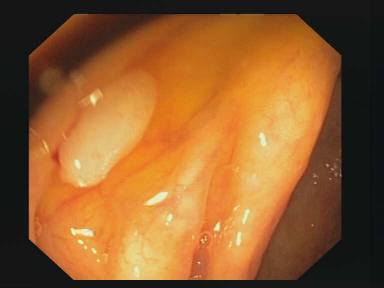

Figure 1: Polyp visual aspects have a wide variety in terms of shape and color. Four different polyps sampled from the different databases considered in this work: (a) Kvasir-Seg [19], (b) CVC-ClinicDB [5], (c) CVC-ColonDB [4], (d) ETIS [29].

The large bowel within the human gastrointestinal tract can be affected by different diseases, among which, Colorectal Cancer (CRC) is particularly concerning. CRC represents the second most common cancer type in women and third most common for men [15]. Gastro-intestinal polyps are known precursors of this type of cancer [34], being present in almost half of the patients over 50 undergoing screening colonoscopies [31]. This kind of lesions show a wide range of shapes and visual appearances, as shown in Fig. 1, turning its identification and segmentation into a challenging problem.